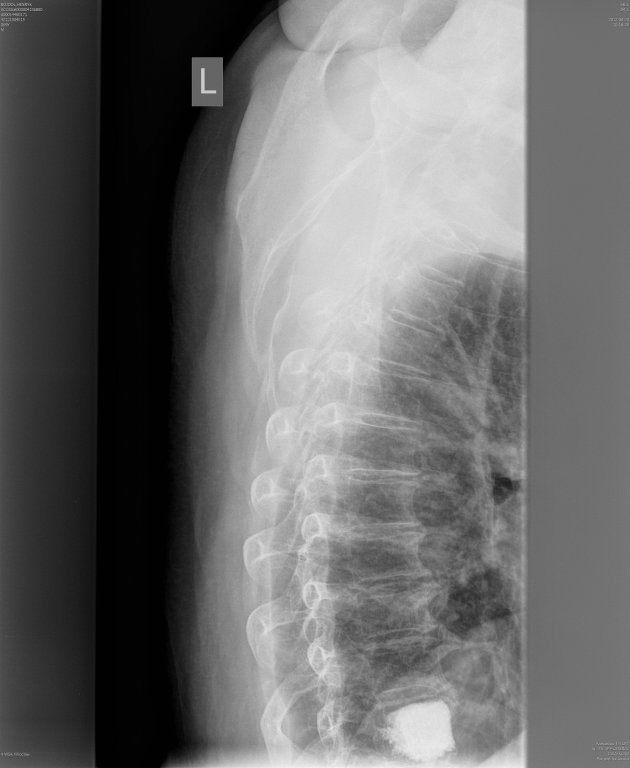

WERTEBROPLASTYKA trzonu TH-10